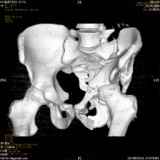

Уважаемые коллеги! Хотелось бы услышать совет по тактике лечения представлленого больного.Поступил после лечения в одном изотделений области. Травма 2,5 месяца назад. После выведенияиз шока был произведен остеосинтез перелома бедра, предплечья, до перевода к нам проводилосьвытяжение по оси шейки бедра за стержень, введенный в большой вертел. На сегодня деформацияригидна, клинически мобильности не определяется. Заранее признателен. P.S. Данный вид травм не включен в перечень "высокотехнологичных операций", направить длялечения по квотам Минздрава очень сложно.

Тяжелый случай... Поздняя реконструкция такого перелома технически сложное дело, вероятность осложнений,неуд.результатов выше(на PubMed article Johnson, Mast, Matta, Letournell results of acetabular reconstruction 20-120 days after injury).

Это обзорные и косые снимки

Привет, Леонид. Оскольчатый высокий двухколонный перелом в такие сроки трогать не надо, т.к. это про такие переломы сказано: "кто с ножом на Ж. пойдет тот в ней и останется...".